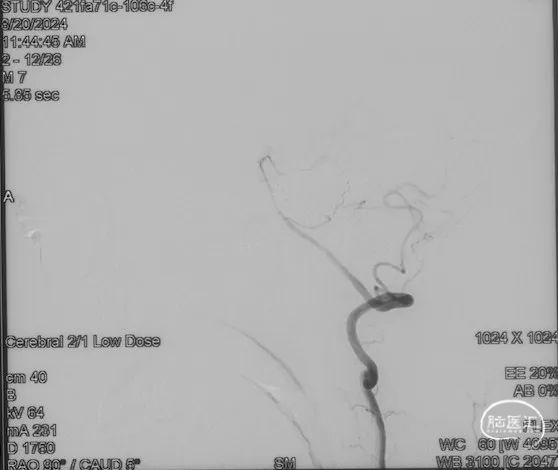

由于瘘口流量大,为了防止栓塞材料过度弥散,并逃逸至深静脉,首先通过Echelon-10微导管向静脉球内填入Feng 12/40、Feng 10/30两枚弹簧圈,限制后续液态栓塞材料仅在静脉起始部弥散。

随后回撤Echelon-10微导管,并通过Echelon-10微导管和Marathon微导管交替注入Onyx-34、Onyx-18,此时可见Onyx首先被血流冲至静脉球内,但被弹簧圈篮筐限制,并在瘘口范围内弥散。

通过“注射-停顿-再注射”,Onyx进一步在瘘口及供血动脉段和引流静脉起始部弥散满意

造影显示瘘口不显影,无静脉早显。

双侧颈外、颈内动脉正侧位造影瘘口均不显影

双侧椎动脉造影未见瘘口显影,可见广泛皮层静脉瘀滞

Onyx胶铸型显示瘘口形态。